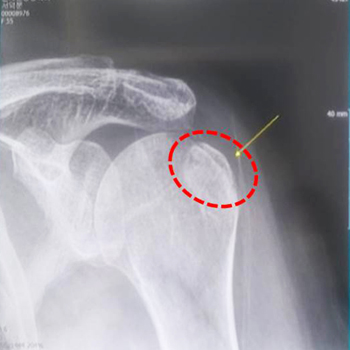

However, the pain did not subside even after a week, so I went to a nearby hospital on Saturday, December 5 and got an X-ray. The doctor said it was a serious injury and referred me to an orthopedic surgeon. The orthopedic ultrasound result showed the left humerus fracture.

The end of my left shoulder blade broke and dislocated, and the tendon was swollen. The doctor said that I might need a surgery depending on the progress.

Simple X-ray

Before prayer: Fracture of the left humerus

After prayer: Synarthrosis of the fractured part